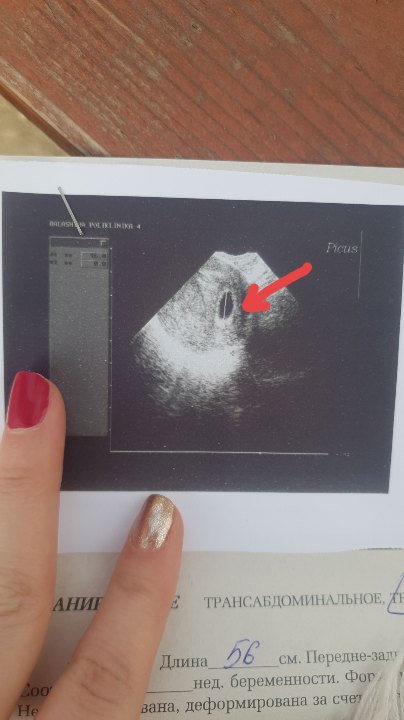

Статьи, видео о беременности, родах, информация о материнствеВсем привет!) Такой вопрос, делали УЗИ, в плодном яйце (16мм) не нашли эмбриона. По хгч срок 4-5 недель, по акушерским 7 недель. Предположительно поздняя овуляция. Это нормально? Или эмбрион может так и не появиться??

Дополняю, сегодня ходила на узи!) Все нашли!) Послушали сердцебиение, 118 ударов) срок поставили 6 недель и 5 дней😊😊

Говорят поздняя овуляция, но помимо нее еще и яйцо в трубах где то встало)